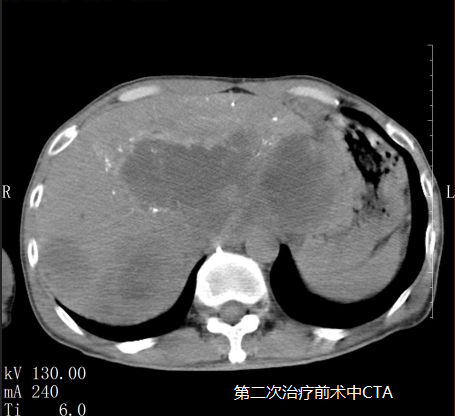

苏先生进行第二次微血管介入治疗后明显感受自己的身体变得轻盈,可以进行简单的饮食,精神状态变好了。

在5月3日苏先生的肝指标检查中甲胎蛋白降为6671IU/ml(参考值0~5.8),随后王峰医生实时跟进苏先生病情为他制定后续的治疗方案,为他开对应的药物治疗;5月14日苏先生的肝指标检查中甲胎蛋白降为18.70U/ml(参考值0~5.8)。

5月18日是苏先生进行第三次微血管介入治疗,治疗后苏先生完全可以自理,饮食恢复正常,面色也慢慢红润起来,肿瘤从原来的16公分缩小至10公分,甲胎蛋白逐渐趋向正常,看到这样的结果也让医生们深感很欣慰,连苏先生也意想不到,前段时间自己还是生命濒危的癌症患者现在却可以像正常人一样生活。他觉得这是上天给他最大的惊喜。